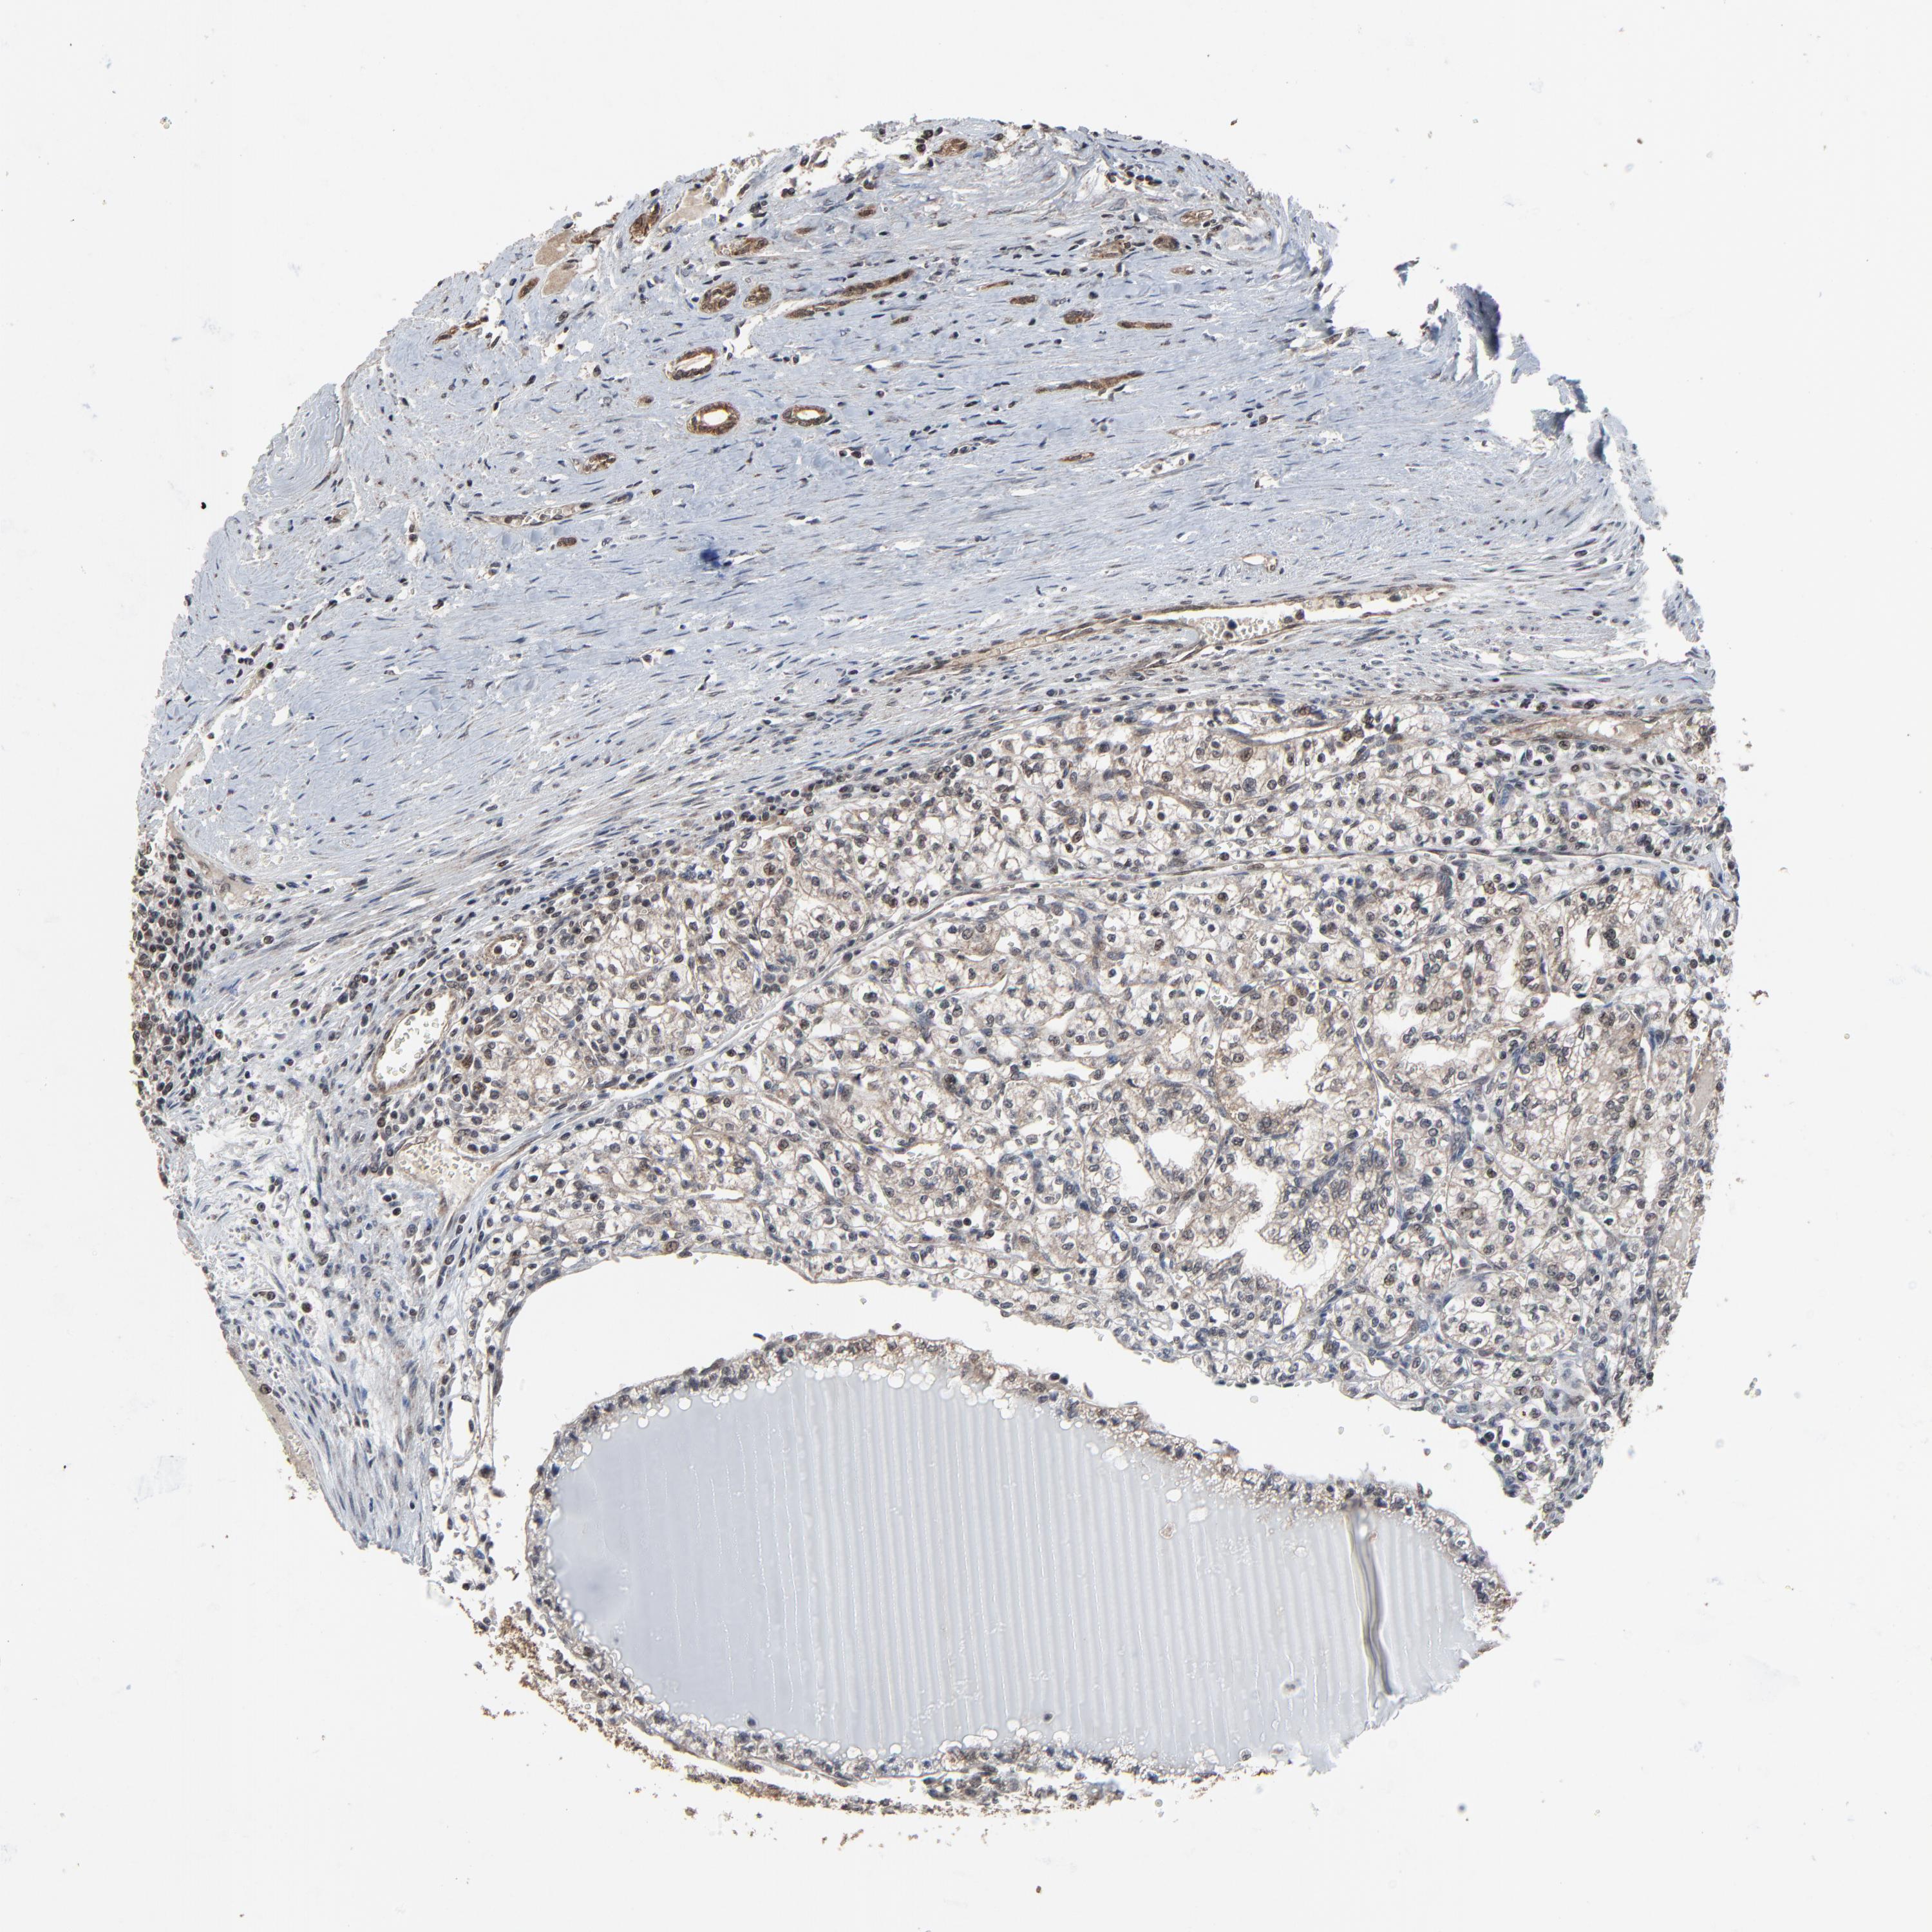

KIDNEY RENAL CLEAR CELL CARCINOMA (VALIDATION) - Interactive survival scatter ploti

The Survival Scatter plot shows the clinical status (i.e. dead or alive) for all individuals in the patient cohort, based on the same data that underlies the corresponding Kaplan-Meier plots. Patients that are alive at last time for follow-up are shown in blue and patients who have died during the study are shown in red.

The x-axis shows the expression levels (FPKM) of the investigated gene in the tumor tissue at the time of diagnosis. The y-axis shows the follow-up time after diagnosis (years). Both axes are complimented with kernel density curves demonstrating the data density over the axes. The top density plot shows the expression levels (FPKM) distribution among dead (red) and alive patients (blue). The right density plot shows the data density of the survived years of dead patients with high and low expression levels respectively, stratified using the cutoff indicated by the vertical dashed line through the Survival Scatter plot. This cutoff is automatically defined based on the FPKM cutoff that minimizes the p-score. The cutoff can be changed by dragging the vertical line or by entering a cutoff value in the square labeled "Current cut-off".

Under the Survival Scatter plot the p-score landscape (black curve; left axis) is shown together with dead median separation (red curve; right axis). Dead median separation is the difference in median mRNA expression between patients who have died with high and low expression, respectively. It is calculated as follows: median FPKM expression of dead patients with high expression - median FPKM expression of dead patients with low expression. This is intended to aid the user in visually exploring custom cutoffs and the associated p-scores and dead median separation.

Individual patient data is displayed and can be filtered by clicking on one or more of the category buttons on the top of the page. Categories describing expression level and patient information include: high, low, alive, dead, female, male and tumor stages. The scale of the x-axis can be toggled between linear and log-scale by clicking on the "x log" button. Mouse-over function shows TCGA ID, patient information and mRNA expression (FPKM) for each patient.

& Survival analysisi

Kaplan-Meier plots summarize results from analysis of correlation between mRNA expression level and patient survival. Patients were divided based on level of expression into one of the two groups "low" (under cut off) or "high" (over cut off). X-axis shows time for survival (years) and y-axis shows the probability of survival, where 1.0 corresponds to 100 percent.

RHOJ is validated prognostic, high expression is favorable in Kidney Renal Clear Cell Carcinoma (validation)

: 18.76

Average pTPM 17.5

Number of samples 100